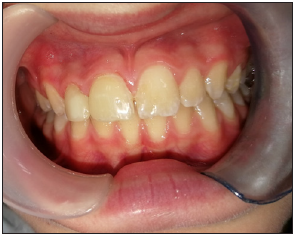

Figure 4:A front view after full restoration.

Figure 5: One year follow up.

The teeth were etched using a 35% phosphoric acid solution (Ultra-Etch™, Ultradent) and coated with 3M™ Single Bond Universal Adhesive. The crowns were then bonded to the teeth using RelyX™ Ultimate Adhesive Resin Cement (3M) and cured. The crowns were polished and occlusal balance was performed (Figure 4). A mouth guard was prepared in order to prevent future dental trauma. At the follow up after one year, the restorations were firm and presented an esthetic outcome (Figure 5).